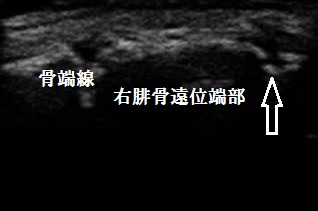

右腓骨遠位端 超音波長軸像 同部3週間後

川越市若葉 小学3年生女児。 左足の痛み、腓骨遠位端部裂離骨折。

超音波検査を実施したところ、左腓骨遠位端部に裂離骨折が認められました(左上矢印の窪み)。

日常生活では包帯でしっかりと固定し、しばらく体育を休むよう指導しました。3週間後の超音波検査では

骨折部の仮骨形成が進み(右上画像の矢印)、骨癒合している様子が認められたため運動を許可し、

治療を終了いたしました。